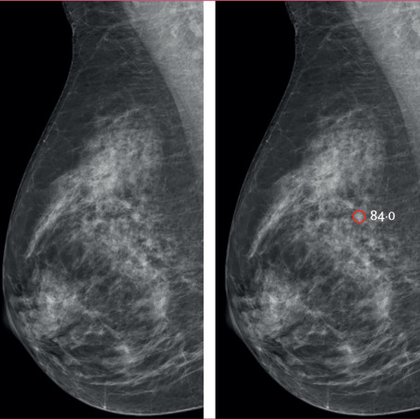

The largest medical #AI randomized controlled trial yet performed, enrolling >100,000 women undergoing mammography screening, was published today @LancetDigitalH The use of A.I. led to 29% higher detection of cancer, no increase of false positives, and reduced workload compared

The findings suggest that AI contributes to the early detection of clinically relevant breast cancer and reduces screen-reading workload without increasing false positives.